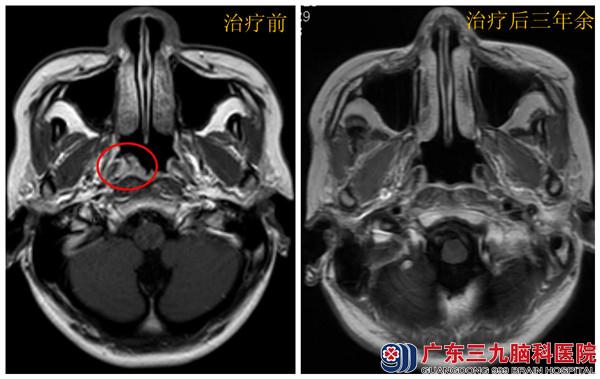

患者刘某,女,27岁,2011年1月无明显诱因出现涕中带血,为间断性,每次量不多,清淡饮食后可缓解,反复出现,无鼻塞、头痛、复视、耳鸣、胸闷、腹痛等特殊不适,未引起重视,症状逐渐加重,2012年12月当地行鼻咽部CT示:右侧鼻咽顶后壁新生物,行鼻咽部活检,病理报告:鼻咽非角化性癌,为进一步治疗,来我院就诊。体查:神清语利,双瞳孔等大等圆约3mm,鼻翼无煽动,口唇无发绀,咽稍红,双扁不大,入院完善相关检查,无颈部淋巴结及身体其他部位转移,诊断:鼻咽非角化性癌(T2N0MO)。

2012年1月行鼻咽部调强放疗,至3月完成,鼻咽部DT:70GY/35F,颈部DT:50GY/25F,余予营养神经、抗炎、漱口、雾化等对症支持治疗,患者治疗过程顺利,未出现严重副反应。目前已治疗后3年余,患者无任何不适主诉,无明显治疗后副反应,现就职一家公司,可正常工作和生活。